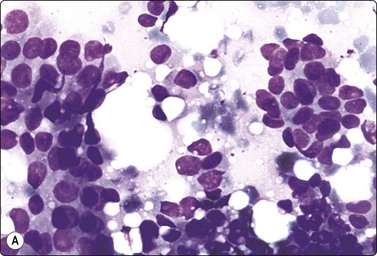

A comparison between the basic benign pattern (non-neoplastic glandular tissue) and the most common malignant pattern (low-grade carcinoma of no special type) in FNB of breast lesions is given in Table 7.2 (Figs 7.2-7.4).

Table 7.2 Comparison of the benign pattern and low-grade carcinoma in FNB smears

Non-neoplastic breast tissue (Figs 7.2A, 7.3A and 7.4A) Low-grade carcinoma NOS (Figs 7.2B, 7.3B and 7.4B)

1. Overall low cell yield 1. Variable but higher cell yield

2. Sheets and aggregates of cohesive, small, uniform cells 2. Irregular clusters of less cohesive, small, mildly irregular cells

3. Small rounded nuclei, bland chromatin, some overlapping 3. Slightly larger and darker nuclei, relatively bland chromatin

4. Myoepithelial cell nuclei among epithelial cells 4. Myoepithelial cell nuclei not seen

5. Variable numbers of single, bare, bipolar nuclei scattered in the background 5. Single cells, most with some cytoplasm, identical to those forming clusters; no bare bipolar nuclei

image image

Fig. 7.2 Non-neoplastic glandular breast tissue and low-grade duct carcinoma

Low-power view; (A) Bimodal population of epithelial sheets and single bipolar nuclei of non-neoplastic glandular breast tissue; (B) Single population of epithelial cells in low-grade carcinoma (MGG, LP).

Fig. 7.3 Non-neoplastic glandular breast tissue and low-grade duct carcinoma

High-power view, air-dried smears; (A) Non-neoplastic glandular breast tissue; (B) Low-grade duct carcinoma. Note single bipolar nuclei in A, and absence of bipolar nuclei, relatively mild nuclear atypia and some loss of cohesion of malignant cells in B (MGG, HP).

Fig. 7.4 Non-neoplastic glandular breast tissue and low-grade duct carcinoma

High-power view, Pap-stained smears; (A) Bimodal population in smear from non-neoplastic breast; (B) Single and clustered cells in low-grade carcinoma; some single cells probably stromal (Pap, HP).